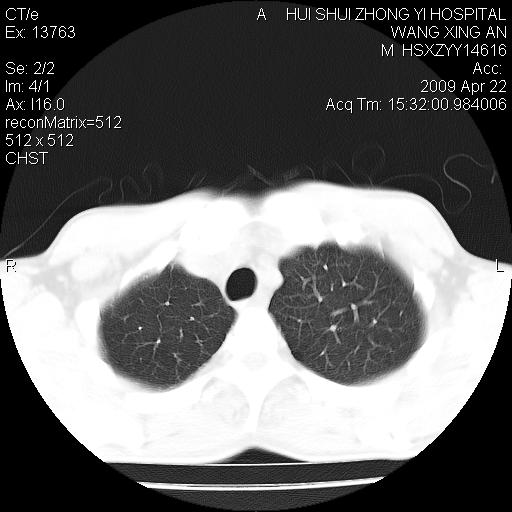

标题: CT19534:患者男、46岁咳嗽、胸痛半月。 [打印本页]

标题: CT19534:患者男、46岁咳嗽、胸痛半月。

考虑---右肺中心型肺癌继发下叶不张,少量胸水。

支持右侧中央型肺ca并右下肺不张、右侧胸腔少量积液。

考虑右侧中心性肺癌并下叶肺不张

右肺纤维灶

右侧少量胸腔积液

1、右下肺中央型肺癌并右肺转移,右肺下叶不张。(肿块围绕右肺下叶支气管生长,致管腔闭塞右肺下叶不张;右肺有结节影)。

2、右侧胸腔积液。

3、右中上肺陈旧性肺结核(右肺见纤维化病灶及点状钙化)。

1)右肺中间段支气管癌并右肺下叶肺不张。2)右肺上叶、两肺下叶背段感染性病变。3)右侧少量胸腔积液。